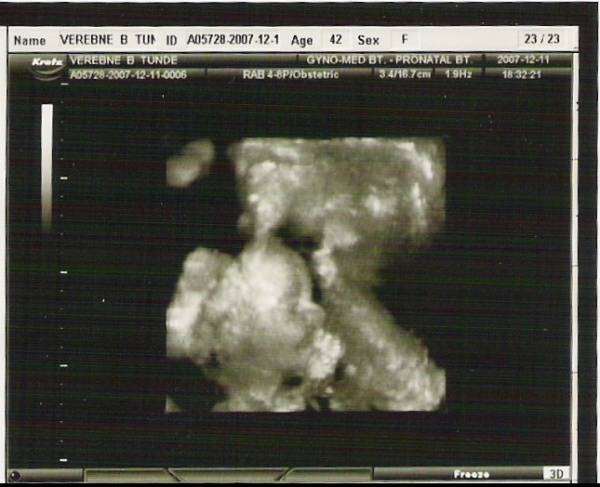

Az uh nem árt a babának, bár ők azt hiszem nem túlságosan szeretik!